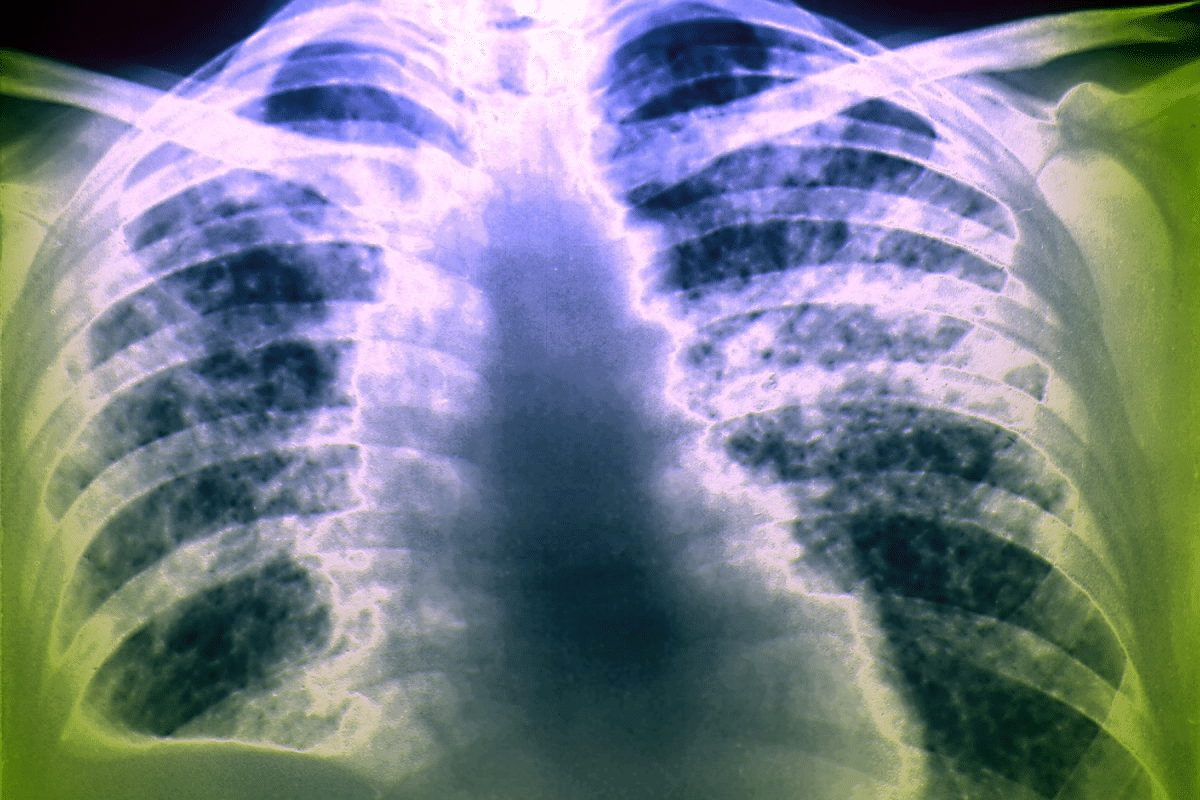

Bronchopneumonia Radiographic Features

Bronchopneumonia, or lobular pneumonia, looks different on X-rays. It has scattered, patchy areas of fluid that don’t stick to one lobe. These spots are small and white, spread out in the lungs. It looks more scattered and less uniform than lobar pneumonia.

Interstitial and Atypical Pneumonia Patterns

Interstitial pneumonia affects the lung’s spaces, like the alveolar septa and bronchovascular bundles. On X-rays, it looks like fine lines or hazy areas, unlike the solid areas seen in other pneumonias. Atypical pneumonia, caused by viruses and Mycoplasma pneumoniae, might show interstitial patterns or a mix of solid and hazy areas.

- Bronchopneumonia: Scattered, patchy areas of consolidation

- Interstitial Pneumonia: Fine, net-like lines or hazy areas